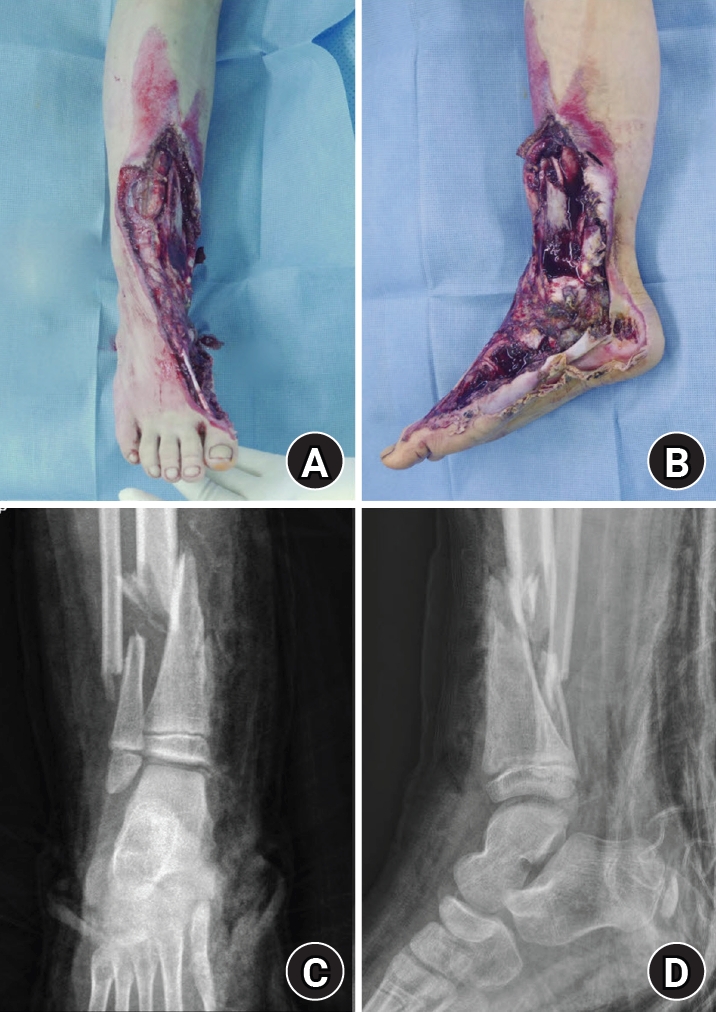

Clinical findings and diagnostic assessment

At presentation, extensive soft-tissue loss of the medial ankle/foot was noted, consistent with a high-energy crush/degloving mechanism (Fig. 1). The wound severity raised concerns for soft-tissue viability, contamination, and subsequent infection risk, and suggested the need for a staged approach with temporary stabilization followed by definitive reconstruction.

Initial plain radiographs demonstrated a distal tibiofibular fracture in a skeletally immature patient, with associated medial-sided midfoot injuries (first metatarsal, medial cuneiform, and medial navicular bone defects) (Fig. 1). During staged management, traumatic loss of the distal tibial medial malleolus was identified, consistent with a Salter-Harris type VI injury pattern and raising concern for physeal bar formation and medial ankle instability due to deltoid ligament deficiency [2,3]. The medial malleolar bony defect was measured intraoperatively as 2.5×2.0 cm to guide graft contouring. Given the severity of the soft-tissue injury, a staged strategy was adopted [1,4].

Fig. 1.

Initial injury on June 14, 2016. (A) Anteroposterior gross photograph obtained at presentation showing a severe crush and degloving injury involving the medial aspect of the right ankle and foot. (B) Lateral gross photograph obtained at presentation demonstrating extensive soft-tissue loss and degloving injury of the medial right ankle and foot. (C) Anteroposterior radiograph obtained at presentation showing an associated distal tibiofibular fracture in a skeletally immature patient. (D) Lateral radiograph obtained at presentation demonstrating the distal tibiofibular fracture.

jmt-2026-00059f1.jpg

Fig. 1. Initial injury on June 14, 2016. (A) Anteroposterior gross photograph obtained at presentation showing a severe crush and degloving injury involving the medial aspect of the right ankle and foot. (B) Lateral gross photograph obtained at presentation demonstrating extensive soft-tissue loss and degloving injury of the medial right ankle and foot. (C) Anteroposterior radiograph obtained at presentation showing an associated distal tibiofibular fracture in a skeletally immature patient. (D) Lateral radiograph obtained at presentation demonstrating the distal tibiofibular fracture.